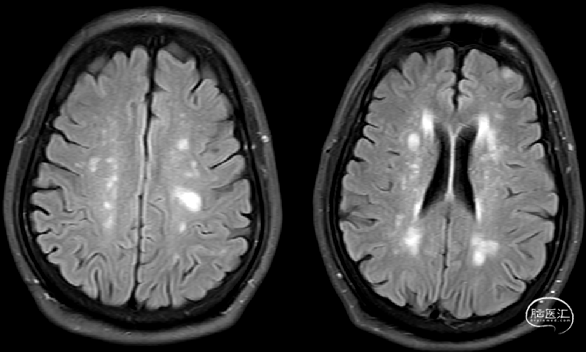

术前CT:左侧基底节区脑梗可能,双侧基底节区、脑室旁腔隙腔梗灶。

术前MRI:左侧额顶叶多发亚急性腔梗灶,双侧额顶叶多发小缺血灶。

FLAIR